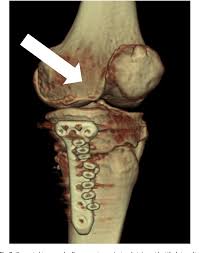

Figure 3 From Impingement Between Medial Plica Against Femoral Condyle Osteophyte After High Tibial Osteotomy Semantic Scholar

Figure 3 From Impingement Between Medial Plica Against Femoral Condyle Osteophyte After High Tibial Osteotomy Semantic Scholar from d3i71xaburhd42.cloudfront.net

The radiographs demonstrated abnormal contour of the medial femoral condyle, consistent with an osteochondral defect, and a fabella posterior to the knee. Methods sixteen knees with a small medial femoral. It acts to support a significant amount of the patient's body weight. An imbalance of the muscles around the knee (some muscles are weaker than others.) overuse (repeated bending or twisting) of the knee joint, especially during sports. If there is a fracture (break) in part of the condyle, this is known as a fracture of the femoral condyle. The medial femoral condyle is supplied by a plexus of vessels from the descending genicular artery and the medial superior genicular artery. Damage may also be the result of a direct blow to the knee. Palpable to either side of the knee joint when it is bent, they are known specifically as the medial and lateral femoral condyles.

A bone fracture at this location is termed a femoral condyle fracture. Tendons and ligaments attach your kneecap to your shinbone and thigh. What is an articular cartilage defect and how is it treated? This is associated with a positive bone scan and, frequently, a radiolucent lesion in the subchondral zone. Damage may also be the result of a direct blow to the knee.